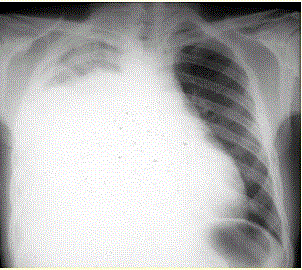

问题  患者男,34岁。进行性胸闷、气促1个月余,伴有干咳、右胸隐痛以及消瘦,无咯血、发热、盗汗、潮热等。 诊断明确后可考虑的治疗方法是(提示 患者经积极处理后上述症状明显好转。1周后已明确诊断。)

选项 A、埋置胸腔导管引流 B、抗感染治疗 C、利尿治疗 D、化学性胸膜固定术 E、全身化疗 F、抗结核治疗 G、外科手术

答案 ADE

解析 ADE